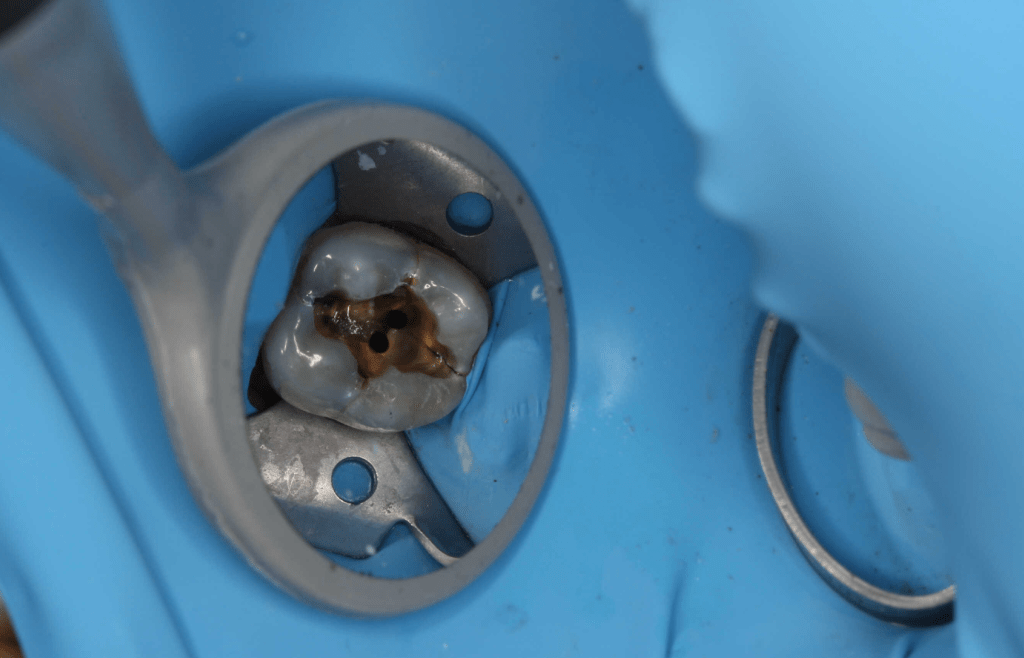

Pulpotomías

Gingivectomía + pulpotomía biodentine + reconstrucción

Pulpotomía biodentine + reco preendio